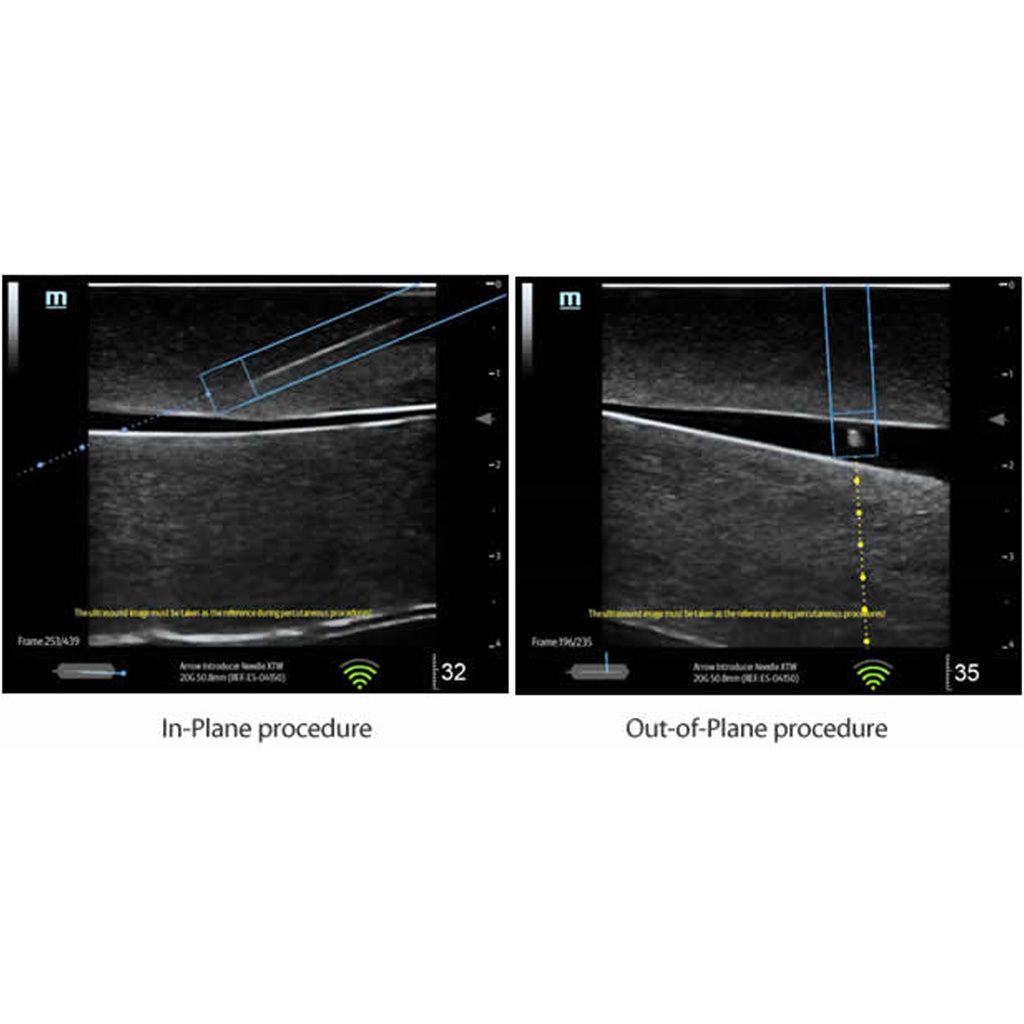

Показва в реално време местоположението и върха на иглата. Съобразявайки посоката на движение на иглата очертава удължителна линия, която помага на оператора да планира траекторията и да измери разстоянието между върха на иглата и целта. Налично за ТЕ5 и ТЕ7.